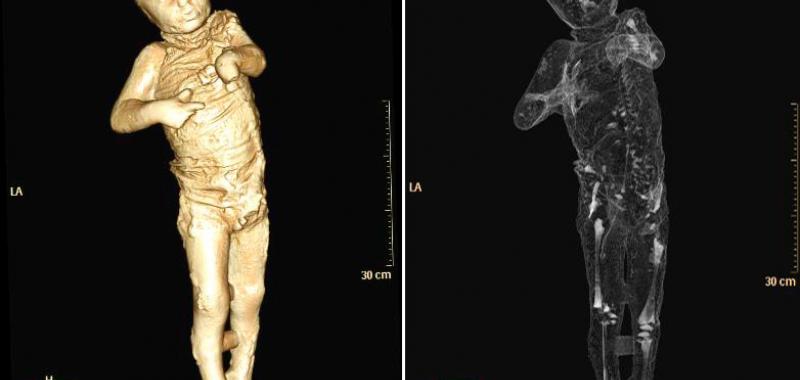

Por primera vez, un grupo de moldes de yeso de Pompeya ha sido sometido a tomografías axiales computerizadas (TAC), a partir de las que ha sido posible determinar la edad, las patologías médicas, los hábitos alimentarios y el estilo de vida de los habitantes de la ciudad arrasada por el Vesubio en el 79 d.C.

El objetivo del estudio radiológico ha sido obtener imágenes del interior de los cuerpos que quedaron conservados en ceniza durante la erupción del volcán, y que luego fueron rellenados con yeso con el propósito de preservar su integridad.

Asimismo, han sido realizados relieves en tres dimensiones de todos los cuerpos mediante técnicas digitales de vanguardia que permiten obtener datos sobre cómo ha variado su estado de conservación en el tiempo.